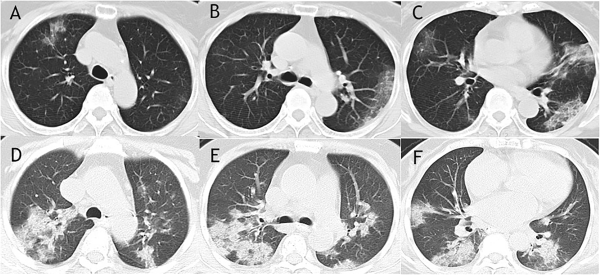

Comparison of lungs of a Wuhan patient who survived COVID-19 — image A-C — to those of a patient who suffered death from the illness — image D-F. Both image sets show the tell-tale ground glass like opacities of COVID-19 in lungs. Image source: Association of Radiologic Findings.